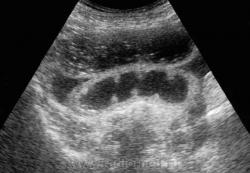

УЗД признаки тонкокишечной непроходимости:

Основные УЗ-признаки при непроходмости, это визуализация расширенных петель тонкой кишки, сниженная перистальтика, свободная жидкость между петлями (танга) и в брюшной полости. Также УЗИ иногда позволяет обнаружить причину обструкции, например опухоль, утолщение стенок терминального сегмента подвздошной кишки при болезни Крона и т.д. УЗИ может решить диагностическую дилемму при неоднозначных рентгенологических признаках на обзорной рентгенограмме брюшной полости. Лимит метода заключается в низкой специфичности при оценки состояния брыжейки, а также зависимость качества диагностики от конституции пациента и опыта оператора.

Тема непроходимости кишечника в результате инвагинации не будет освещена в даннoм обзоре, она хорошо описана в многих отечественных и зарубежных публикациях. Думаю что все коллеги занимающиеся данной проблемой знают что определяющее значение в диагностике инвагинации пренадлежит УЗ-диагностике. На нашем сайте ранее было размещено показательное наблюдние:

примеры сонограмм с расширенными петлями тонкой кишки

УЗИ позволяет прекрасно лоцировать свободную жидкость в брюшной полости